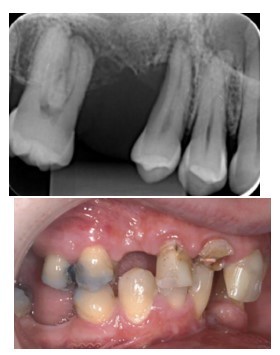

evaluation of potential abutments when designing and planning bridges (8)

options for bridge design (3 main groups with subgroups)

Compare advantages and disadvantages of each design